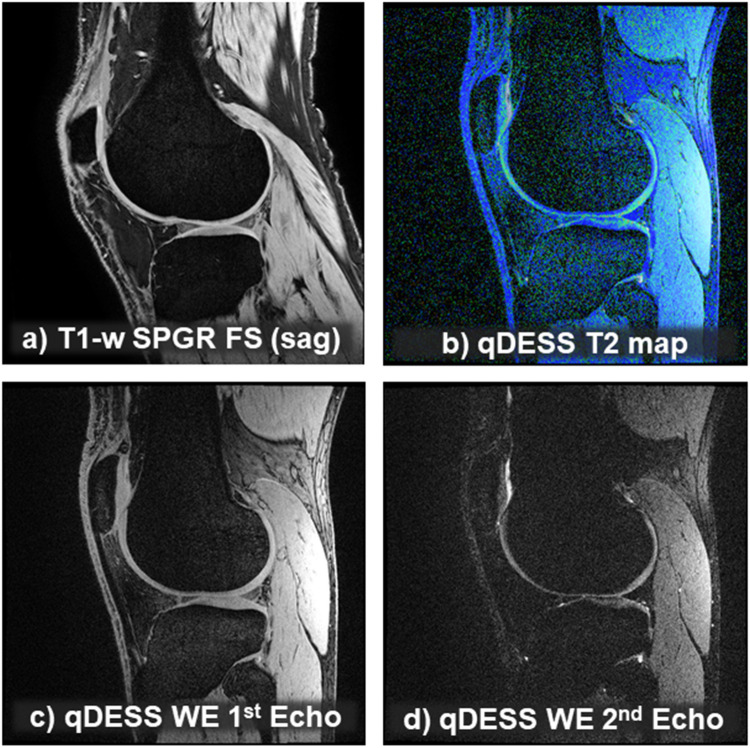

骨关节炎是一种累及所有骨关节组织的衰弱性全器官疾病。监管机构尚未批准有效的治疗方法来改变这种疾病的自然史及其结构进展。在本白皮书中,我们将总结“多面”(多对比)磁共振成像(MRI)的概念,重点介绍其在骨关节炎临床试验中的应用。这里描述的过程包括一个紧密相连的价值和精度链,其中所有元素必须无缝地对齐,以使试验成功。该程序应从仔细的患者特征和选择开始,可能辅以(多方面)成像,以便这些潜在参与者的疾病(亚)类型与医学研究产品(即所研究的药物)的作用机制(MOA)相匹配。接下来应该是一个全面而有效的MRI采集方案,采用具有各种对比的序列,以表征基于成像的关节病理和评估药物的MOA。必须使用合适的图像分析工具,理想情况下要遵守法规遵从标准。根据严格的先验规则,可以从各种(多面)对比中派生出多个验证端点,并可能组合成多组分或复合端点。总之,一个强大的价值和精确链需要是一个完整的功能,以改善疾病骨关节炎试验是成功的。参与者的选择必须注意药物的MOA,并且应该有一个对齐良好的定制的“多面”图像采集方案,合适的图像分析工具和有意义的终点,这些应该与特定的图像对比相匹配。

Osteoarthritis is a debilitating, whole-organ disease that involves all osteoarticular tissues. No effective treatments have yet been approved by the regulatory agencies for modifying the natural history of this disease and its structural progression. In this whitepaper, we will summarize concepts of "multi-faceted" (multi-contrast) magnetic resonance imaging (MRI), with a focus on its application in osteoarthritis clinical trials. The process described here encompasses a tightly interlinked value and precision chain, where all elements must be aligned seamlessly for the trial to succeed. The procedure should begin with careful patient characterization and selection, potentially aided by (multifaceted) imaging, so that the disease (sub-) types in these potential participant will match the mechanism of action (MOA) of the medical investigational product (i.e., the drug studied). This should be followed by a comprehensive yet efficient MRI acquisition protocol, employing sequences with various contrasts that permit the characterization of imaging-based joint pathologies and evaluation of the drug's MOA. Suitable image analysis tools must be employed, ideally adhering to regulatory compliance standards. Multiple validated endpoints can be derived from the various (multifaceted) contrasts, to be potentially combined to multi-component or composite endpoints, based on stringent a-priori rules. In conclusion, a robust value and precision chain needs to be fully functional for a disease-modifying osteoarthritis trial to be successful. Participant selection must be mindful of the drug's MOA, and a well-aligned and custom-tailored "multifaceted" image acquisition protocol, suitable image analysis tools, and meaningful endpoints should be in place, which should match the specific image contrasts.